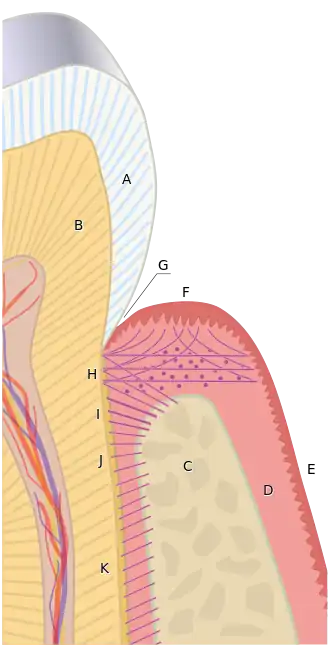

Periodontology or periodontics (from Ancient Greek περί, perí – 'around'; and ὀδούς, odoús – 'tooth', genitive ὀδόντος, odóntos) is the specialty of dentistry that studies supporting structures of teeth, as well as diseases and conditions that affect them. The supporting tissues are known as the periodontium, which includes the gingiva (gums), alveolar bone, cementum, and the periodontal ligament. A periodontist is a dentist that specializes in the prevention, diagnosis and treatment of periodontal disease and in the placement of dental implants.[1]

The term periodontium is used to describe the group of structures that directly surround, support and protect the teeth. The periodontium is composed largely of the gingival tissue and the supporting bone.[2]

Normal gingiva may range in color from light coral pink to heavily pigmented. The soft tissues and connective fibres that cover and protect the underlying cementum, periodontal ligament and alveolar bone are known as the gingivae. The gingivae are categorized into three anatomical groups: the free, attached and the interdental gingiva. Each of the gingival groups are considered biologically different; however, they are all specifically designed to help protect against mechanical and bacterial destruction.[3]

The tissues that sit above the alveolar bone crest are considered the free gingiva. In healthy periodontium, the gingival margin is the fibrous tissue that encompasses the cemento-enamel junction, a line around the circumference of the tooth where the enamel surface of the crown meets the outer cementum layer of the root. A natural space called the gingival sulcus lies apically to the gingival margin, between the tooth and the free gingiva. A non-diseased, healthy gingival sulcus is typically 0.5-3mm in depth, however, this measurement can increase in the presence of periodontal disease. The gingival sulcus is lined by a non-keratinised layer called the oral sulcular epithelium; it begins at the gingival margin and ends at the base of the sulcus where the junctional epithelium and attached gingiva begins.[4]

The junctional epithelium is a collar-like band that lies at the base of the gingival sulcus and surrounds the tooth; it demarcates the areas of separation between the free and attached gingiva. The junctional epithelium provides a specialized protective barrier to microorganisms residing around the gingival sulcus.[4] Collagen fibres bind the attached gingiva tightly to the underlying periodontium including the cementum and alveolar bone and vary in length and width,[4] depending on the location in the oral cavity and on the individual.[5][6] The attached gingiva lies between the free gingival line or groove and the mucogingival junction. The attached gingiva dissipates functional and masticatory stresses placed on the gingival tissues during common activities such as mastication, tooth brushing and speaking.[7]: 80–81 In health it is typically pale pink or coral pink in colour and may present with surface stippling or racial pigmentation.[7]

The periodontal ligament is the connective tissue that joins the outer layer of the tooth root, being the cementum, to the surrounding alveolar bone. It is composed of several complex fibre groups that run in different directions and which insert into the cementum and bone via Sharpey's fibres.[4] The periodontal ligament is composed mostly of collagen fibres, however it also houses blood vessels and nerves within loose connective tissue.[6] Mechanical loads that are placed on the teeth during mastication and other external forces are absorbed by the periodontal ligament, which therefore protects the teeth within their sockets.[7]

In periodontal health, the alveolar bone surrounds the teeth and forms the bony socket that supports each tooth. The buccal and lingual plates and lining of the sockets are composed of thin, yet dense compact or cortical bone.[3] Within the cortical plates and dental sockets lies cancellous bone, a spongy or trabecular-type bone which is less dense than compact bone.[6] The anatomic landmarks of the alveolar process includes the lamina dura, the alveolar crest, and the periodontal ligament space.[9]

Cementum is the outer layer of the tooth root; it overlies the dentine layer of the tooth and provides attachment for the collagen fibres of the periodontal ligament. It also protects the dentine and provides a seal for the otherwise exposed ends of the dentinal tubules. It is not as hard as enamel or dentine and is typically a light yellow colour.[7]